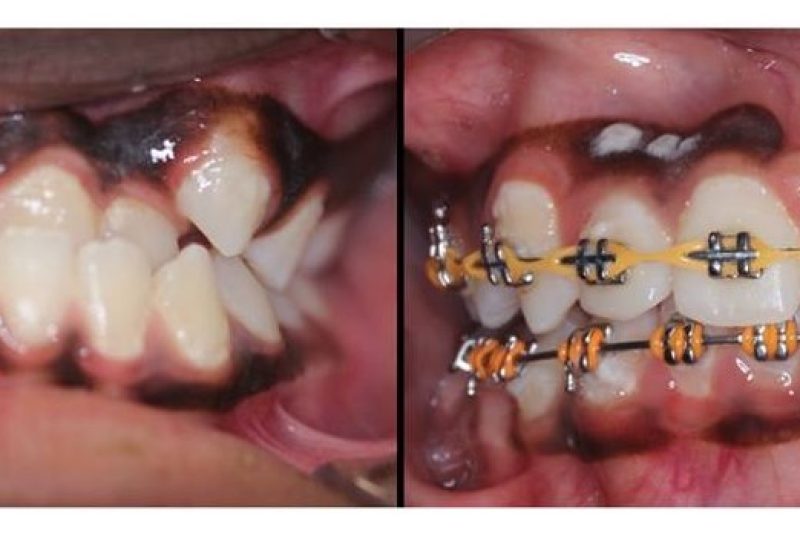

Been doing this for 19y, but I’m still amazed how my work can change a person’s look/life in just a year!